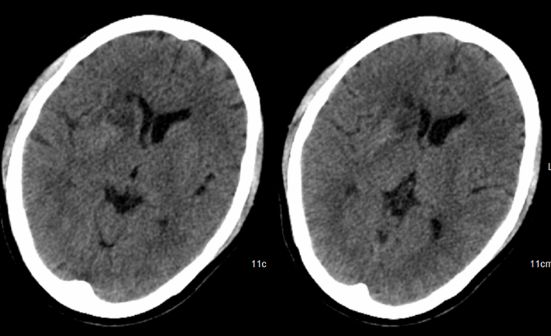

完善术前检查后,经科室讨论,考虑胶质瘤可能性大。但由于病变位置较深,直接行开颅切除术风险大,也可先行穿刺活检术明确诊断。与患者家属沟通后,其选择后者。遂择期行立体定向穿刺活检术,手术过程顺利。术中冰冻提示:胶质细胞增生伴血管增生,考虑胶质瘤。术后复查CT提示:穿刺术后改变,穿刺部位未见明显出血,病灶呈低密度(图2)。

图2.术后复查CT提示:穿刺部位未见明显出血,病灶呈低密度。